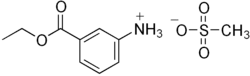

Tricaine mesylate

| Formula | C10H15NO5S |

| Molar mass | 261.29 g·mol−1 |